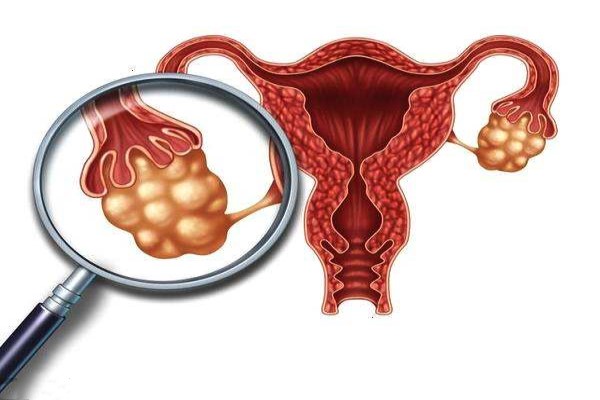

多囊卵巢综合征是一种常见的妇科疾病,也是试管婴儿常见的适应症,影响5-20%育龄女性,最常见的特征包括月经周期紊乱或延长、雄激素水平升高、卵巢出现大量囊肿,并最终...

多囊卵巢综合征(PCOS)是最常见的内分泌失调之一,也是试管婴儿常见的适应症。 PCOS无法自愈,但研究表明饮食和生活方式的改变可以帮助控制病情。如果患有PCOS...

多囊卵巢综合征(多囊卵巢综合症)是一种复杂的疾病,影响约10%的育龄妇女。患有多囊卵巢综合症的女性可能会出现各种症状,包括情绪变化和皮肤状况(痤疮,面部毛发过多)...

多囊卵巢综合症是妇产科常见的一种内分泌兼代谢性疾病。病因迄今没有完全阐明,认为是遗传学基础上、环境因素参与的发病,也就是说,家族成员如果有肥胖、父系秃发、母系月经...

多囊卵巢综合症(PCOS)的特征表现为卵巢功能紊乱和高雄激素表现,是不孕症女性最常见的病因。PCOS女性常因月经紊乱而就诊于妇科医生,主诉多为高雄激素而产生的症状...

多囊卵巢综合征(PCOS)是以月经不规则(常见月经稀发、月经间期不规则阴道流血)、超声影像卵巢多囊改变和高雄激素血症为特征的综合征,是生育年龄妇女常见的代谢和内分...

多囊卵巢综合征(PCOS)是育龄期妇女最常见的内分泌和代谢紊乱性疾病,是引起无排卵性不孕的主要原因,一般认为它与遗传、胰岛素抵抗、下丘脑—垂体—卵巢轴功能异常、肾...

多囊卵巢综合征(PCOS)是一个女性常见的健康问题,影响约10%的育龄妇女。患有PCOS的女性有激素不平衡和新陈代谢问题,可能影响女性的整体健康和外貌。PCOS也...

多囊卵巢综合征(polycystic ovary syndrome,PCOS)是一种常见的青春期和育龄期妇女内分泌紊乱性疾病, 4%~18% 的育龄期妇女受其影响...